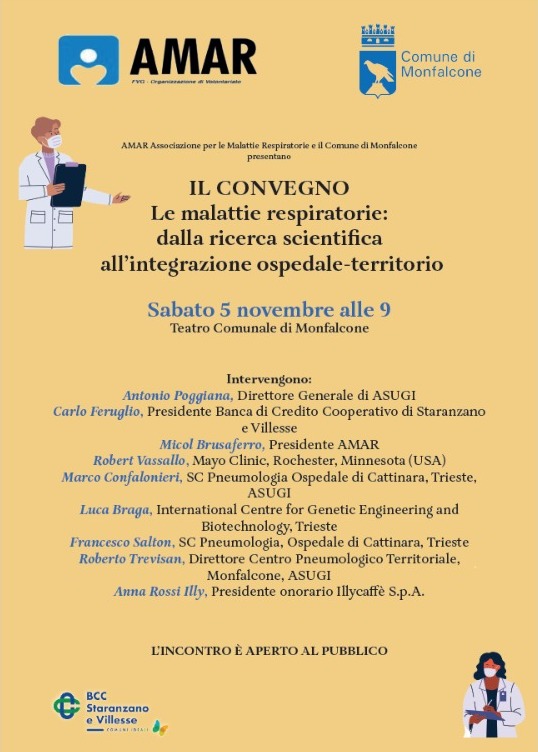

Monfalcone

Monfalcone

Monfalcone

L'Associazione LILT, che si distingue per l'impegno a livello nazionale nella lotta contro i tumori attraverso campagne informative, ricerca scientifica, pubblicazioni di opuscoli, educazione sanitaria, interventi nelle scuole, eventi, esami e controlli periodici effettuabili presso gli ambulatori delle Sezioni Provinciali, oltre[...] Vai alla notizia

Monfalcone

Monfalcone

Il primo evento si snoda tra la Rocca e le trincee del Parco Tematico della Grande Guerra di Monfalcone, valorizzando quei segno che il conflitto ha lasciato sul territorio. Sabato 9 alle ore 9:30 l’esperto Grande Guerra FVG Roberto Todero guiderà una visita guidata tra i sentieri carsici alle spalle di Monfalcone.[...] Vai alla notizia

Monfalcone

Il primo evento si snoda tra la Rocca e le trincee del Parco Tematico della Grande Guerra di Monfalcone, valorizzando quei segno che il conflitto ha lasciato sul territorio. Sabato 9 alle ore 9:30 l’esperto Grande Guerra FVG Roberto Todero guiderà una visita guidata tra i sentieri carsici alle spalle di Monfalcone.

[...] Vai all'evento

Monfalcone

Due intense giornate di incontri per l'economia del mare e domani partecipazione alla Barcolana con un proprio stand incentrato sulla sostenibilità. L’inaugurazione è alle ore 12. La partecipazione rientra in un progetto di attenzione alle opportunità del mare, definito FramesPort. Da oggi sono presenti[...] Vai alla notizia

Monfalcone

“Il lavoro è un diritto previsto dalla Costituzione e il lavoro dà dignità alla persona”. È con questa premessa che il Sindaco Anna Maria Cisint e l’Amministrazione di Monfalcone hanno avviato l’ampliamento e il potenziamento del centro tamponi presso la farmacia Comunale n. 2 di[...] Vai alla notizia